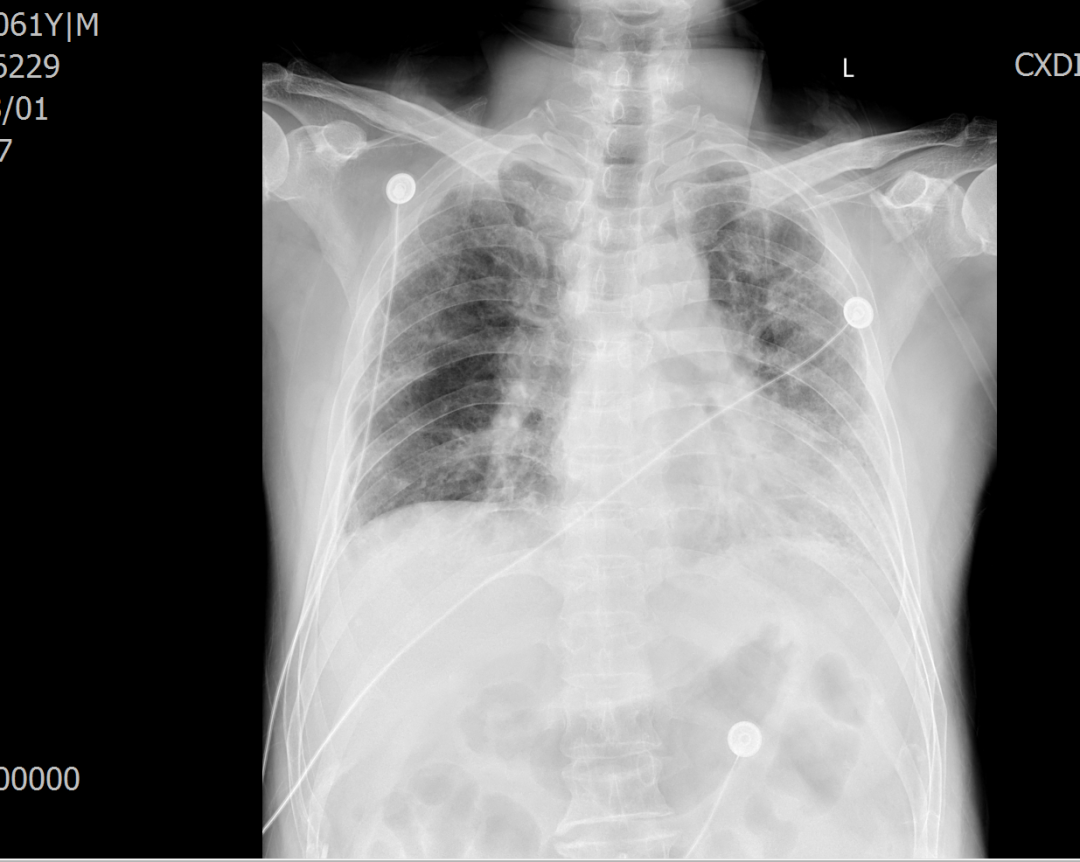

对冷冻肺活检术的必要性和并发症充分知情后,患者及家属签署同意书,罗少华主任带领学科团队在手术室全麻下为患者成功实施了TBCB,取得肺组织标本,术中出血少,患者未出现气胸等并发症,术后恢复良好,经病理确诊为寻常型间质性肺炎,为患者制定精准治疗方案提供了重要的依据。

术后复查胸片,未见气胸、血胸等并发症